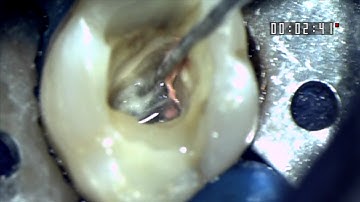

Glide Path Management - Working Length & Patency